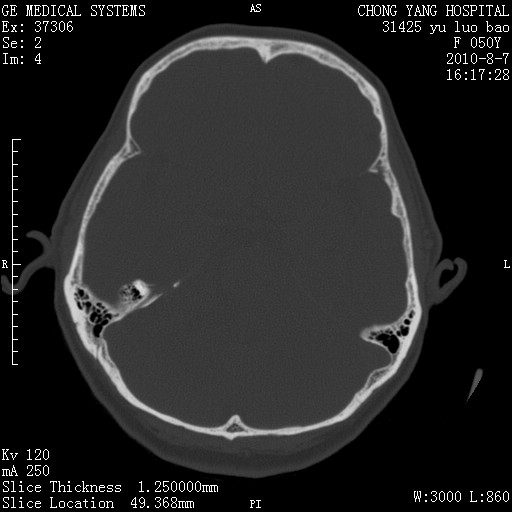

标题: CT28285:听力下降一年,头昏。 [打印本页]

标题: CT28285:听力下降一年,头昏。

骨窗示右侧内听道扩大,考虑右侧听神经瘤。